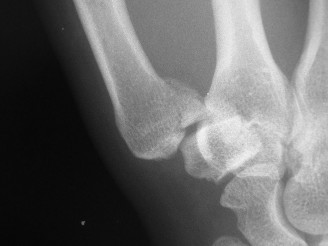

A 24-year-old male sustained an injury to his right thumb while skiing. He was holding onto a ski pole when h…